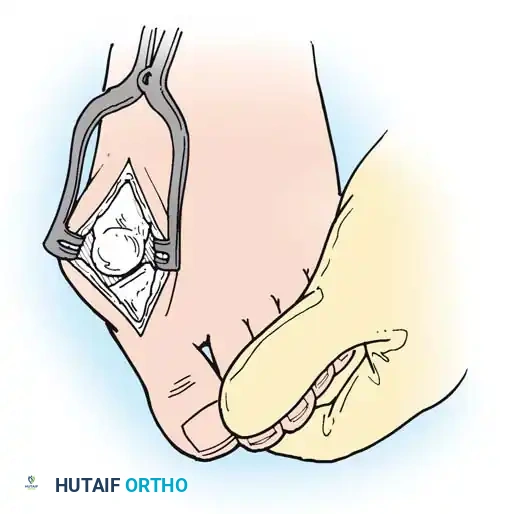

Surgical Diagrams demonstrating the principles of first MTP arthrodesis and lesser metatarsal head resection to restore a functional, plantigrade forefoot cascade.

1. Approach: A dorsal longitudinal incision is made medial to the EHL tendon, extending from the mid-shaft of the first metatarsal to the interphalangeal joint.

2. Joint Preparation: The capsule is incised, and the collateral ligaments are released. The severely eroded articular surfaces of the first metatarsal head and the base of the proximal phalanx are resected. Cup-and-cone reamers are highly recommended to preserve length while allowing multi-planar adjustment.

3. Positioning: The hallux is positioned in 10 to 15 degrees of valgus and 15 to 20 degrees of dorsiflexion relative to the first metatarsal shaft. Neutral rotation must be confirmed to ensure the toenail faces directly dorsal.

4. Fixation: Rigid internal fixation is achieved using a dorsal contoured titanium plate and a lag screw across the arthrodesis site.

- Approach: Two dorsal longitudinal incisions are typically utilized (one centered between the 2nd and 3rd rays, and one between the 4th and 5th rays) to access all lesser MTP joints while preserving dorsal skin bridges. Alternatively, a transverse plantar approach can be used if severe plantar callosities require excision.

- Resection: The extensor tendons are retracted or lengthened (Z-plasty). The dorsal capsule is opened, and the collateral ligaments are sharply divided to allow plantarflexion of the metatarsal.

- Osteotomy: An oscillating saw is used to resect the metatarsal heads at the anatomical neck. It is imperative to create a smooth, parabolic cascade (the 2nd metatarsal should be the longest, tapering down to the 5th).

- Soft Tissue Balancing: The plantar plate and fat pad, which have migrated distally, are mobilized and pulled proximally under the remaining metatarsal stumps. If the toes remain contracted, closed osteoclasis or PIP joint resection arthroplasties may be performed.

- Pinning: Smooth Kirschner wires (K-wires) are driven antegrade through the toes and retrograde into the metatarsal shafts to hold the toes in neutral alignment.

Intraoperative view demonstrating the exposure and resection of the lesser metatarsal heads to decompress the forefoot and allow reduction of the dislocated digits.